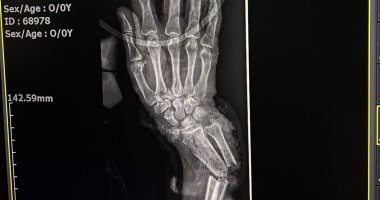

اليوم السابع - إنقاذ حالتين من بتر مؤكد فى إنجاز طبي بمستشفى سوهاج الجامعى